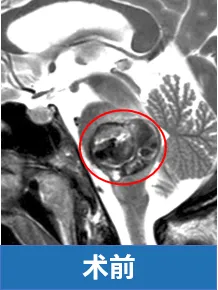

45岁这一年,患者的生活被脑干内破裂的海绵状血管瘤彻底改变。起初认为这种良性血管瘤无需过度担忧,至少不会引发严重出血。但当患者卧床不起,身体半侧瘫痪,面部歪斜时,才真正意识到问题的严重性。

但医生同时指出,病灶位于"手术禁区"脑桥区域,病变已使脑桥膨胀如气球。脑桥作为脑干中段结构,上接中脑,下连延髓,承担大脑、小脑与脊髓间的关键连接功能。其腹侧面明显隆起,表面沟回复杂,内部有大量横向神经纤维延伸至小脑,负责协调大脑与小脑间的信息传递;背侧参与构成第四脑室底上部,内含三叉神经核、展神经核等重要结构,调控面部感觉、眼球运动、听觉和平衡功能。

此外,脑桥深部还存在网状结构等生命中枢,对维持意识清醒、睡眠节律和呼吸功能具有重要作用。由于脑桥结构极其复杂,手术操作需毫米级精度,历来被视为神经外科手术的高风险区域。

值得庆幸的是,巴特朗菲教授接手了这例高风险手术。在精细清除血肿及血管畸形的同时,特别注意保护脑桥后部实质及外展神经、面神经的完整性。术后一年随访显示,患者面神经和外展神经功能基本恢复,能自然露出真诚笑容。患者最终恢复至病前状态,曾经的恐惧感被稳定的踏实感取代。这完全得益于教授精湛的手术技术,将濒临危险的患者成功救治。